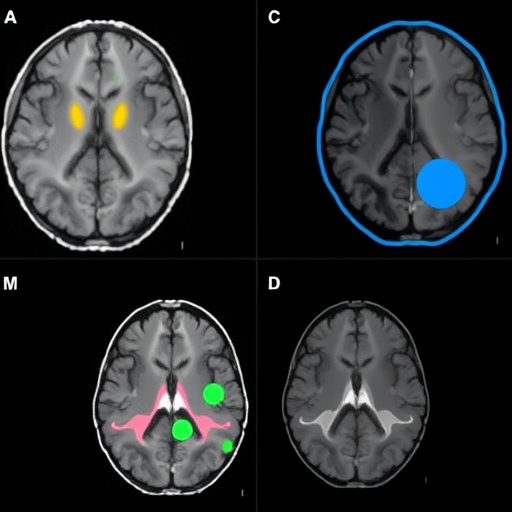

In the study, the researchers recruited a cohort of Parkinson’s patients undergoing STN DBS and employed advanced fMRI protocols optimized to record brain activity during stimulation sessions. By synchronizing the imaging with the delivery of DBS pulses, they were able to precisely capture the spatial and temporal patterns of neural activation. Crucially, rather than focusing solely on global brain changes, the analysis was finely tuned to dissect symptom-specific circuits, allowing differentiation between tremor-dominant and akinetic-rigid phenotypes. This approach marks a paradigm shift away from viewing STN DBS effects as uniformly distributed, instead emphasizing the heterogeneity of symptom-driven network modulation.

The results revealed strikingly distinct activation maps associated with different Parkinson’s symptoms. For patients presenting predominantly with tremor, DBS elicited significant activation in cerebellar-thalamo-cortical pathways. This finding aligns with a growing body of evidence implicating cerebellar circuits in tremor generation and modulation. In contrast, patients with predominant akinesia and rigidity exhibited enhanced activation in fronto-striatal networks, including motor and premotor cortices, underscoring the diverse neural substrates of various symptom dimensions. These findings not only deepen our understanding of Parkinsonian pathophysiology but also hint at tailored DBS programming strategies that could optimize therapeutic outcomes based on individual symptom profiles.

Furthermore, the investigation extended beyond mere localization of activation, employing functional connectivity analyses to elucidate how network dynamics shift in response to STN stimulation. These analyses revealed that DBS not only modulates focal regions but also orchestrates widespread network-level reconfigurations that correlate with symptom relief. For example, tremor improvement was paralleled by strengthened connectivity within cerebellar loops, while rigidity amelioration corresponded to enhanced coupling between motor cortical areas and the basal ganglia. Such insights emphasize the importance of conceptualizing DBS effects at the systems neuroscience level, integrating multiple brain regions and pathways.

From a technological perspective, the utilization of ultra-high-field 7 Tesla MRI scanners provided exceptional spatial resolution, allowing visualization of small subcortical structures and their connectivity in unprecedented detail. This level of resolution was critical for disentangling overlapping activation in densely interconnected regions like the basal ganglia, thalamus, and cerebellum. As imaging technologies continue to evolve, we can anticipate further refinements in our understanding of DBS-mediated neuromodulation at microcircuit levels.